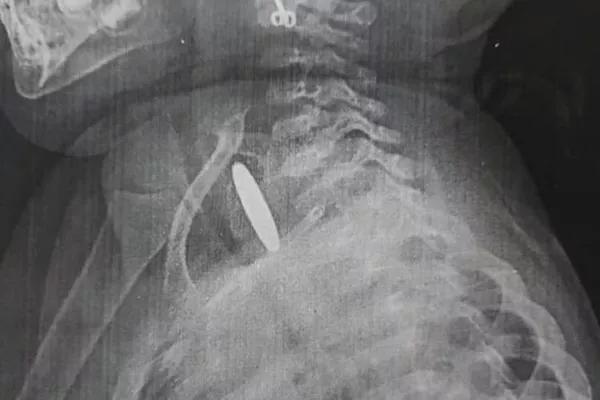

В Оше двухлетняя девочка проглотила монету — предмет 2 месяца был в ее пищеводе

БИШКЕК, 11 сен — Sputnik. В Оше двухлетняя девочка проглотила монету. Посторонний предмет два месяца был в ее пищеводе. Об этом сообщает Ошская межобластная детская клиническая больница.

Посторонний предмет два месяца был в ее пищеводе

По словам врачей, родители и родственники все это время не замечали неладного. Ребенок иногда кашлял, в остальном все было нормально. Девочку прооперировали в межобластной больнице. Сейчас состояние ребенка хорошее. Врачи призывают родителей следить за детьми.